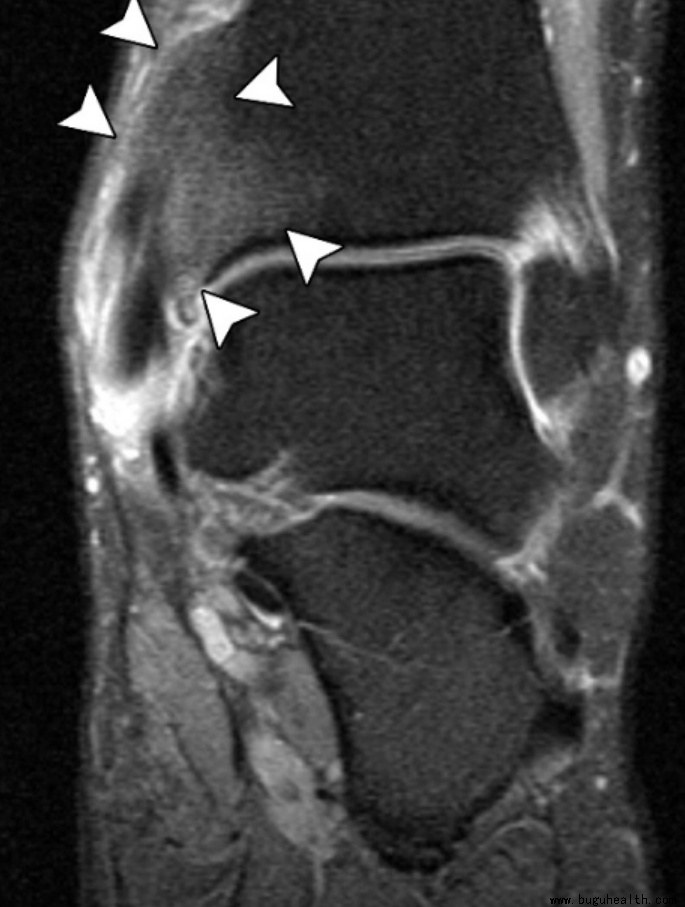

在医院医生常用的影像学检查为负重足部X线检查来评估足弓扁平、后足外翻和前足外展的情况,利用超声或MR来评估肌腱(胫骨后肌腱)和韧带病变(弹簧韧带和骨间韧带)情况。三维CT重建可以分析骨骼和关节形态,评估骨关节炎情况,并有助于制定截骨手术方案。

冠状位MR图像显示踝部(箭头)的骨肥大和骨髓水肿、胫后肌腱增厚伴撕裂